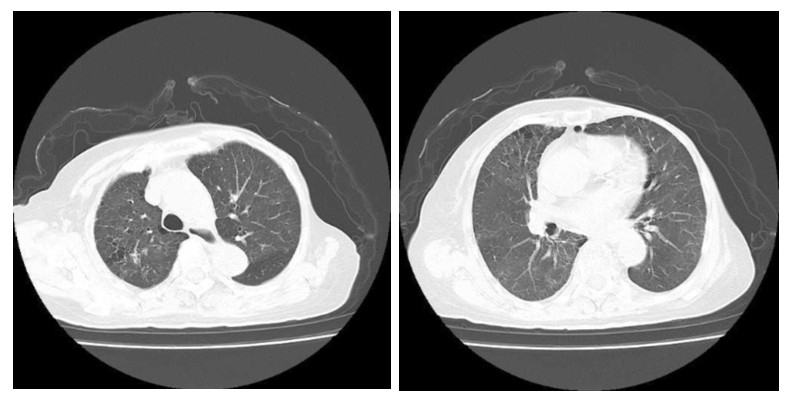

入院查体:体温37.8℃,心率92次/min,呼吸30次/min,血压108/65 mmHg(1 mmHg=0.133 kPa)。神志清楚,查体可配合,皮肤黏膜未见异常,浅表淋巴结未及肿大。口唇轻度紫绀,颈静脉充盈,双肺呼吸音粗, 双肺可闻及湿啰音。心律不齐,主动脉瓣区及三尖瓣膜区可闻及3/6级收缩期杂音。腹软、无压痛及反跳痛。双下肢轻度凹陷性水肿。辅助检查:血常规:白细胞(WBC)9.29×109/L、中性粒细胞计数(NEUT)8.14×109/L、淋巴细胞绝对值:0.78×109/L、红细胞计数(RBC)2.90×1012/L、血红蛋白(HGB)86.00 g/L、血小板计数(PLT)134.00×109/L。C反应蛋白(CRP)114.11 mg/L,白介素6(IL-6)45.30 pg/mL,降钙素原(PCT)0.54 ng/mL。总胆红素(TBIL):27.65 μmol/L、白蛋白(ALB)29.00 g/L、丙氨酸氨基转移酶(ALT)30.06 U/L、天门冬氨酸氨基转移酶(AST)41.30 U/L。肌酐(Scr)98.20 μmol/L、尿酸(UA)453.60μmol/L、尿素氮(BUN)13.38 mmol/L。钾(K+)3.01 mmol/L、氯(Cl-):109.09 mmol/L、钙(Ca2+)1.99 mmol/L。高敏肌钙蛋白Ⅰ(cTnI)78.30 pg/mL、肌红蛋白(Mb)88.10 ng/mL、B型尿钠肽(BNP)449.80 pg/mL。血沉(ESR)104.0 mm/h,类风湿因子(RF)37.67 IU/mL,补体C3:0.70 g/L、补体C4:0.17 g/L。尿液分析:隐血+3、白细胞+1、尿蛋白+3。凝血功能:D-二聚体:0.78 μg/mL、余正常。血气分析:pH 7.376、PaCO2 31.3 mmHg、PaO2 65.4 mmHg(鼻导管吸氧,FiO2: 30%)、BE-4.2 mmol/L、HCO3- 20.3 mmol/L、Lac 0.9 mmol/L。1, 3-β-D葡聚糖检测阴性,结核抗体、TORCH十项、呼吸道九项、EB病毒均为阴性。心电图示:窦性心律;室性早搏伴有长QTc间期。心脏彩超:三尖瓣少量反流。左室舒张功能减低。胸部CT:双肺感染,双肺见多发磨玻璃样及片状高密度影,部分实变(图 1)。入院初步诊断:①呼吸衰竭;②重症肺炎;③咯血待查;④轻度系统性红斑狼疮;⑤左心功能不全NYHA分级Ⅲ级;⑥心律失常室早;⑦电解质代谢紊乱低钾、低钙血症;⑧左乳腺癌术后;⑨左侧髋关节置换术后。予美罗培南(1.0 g, ivgtt, q8h)+左氧氟沙星氯化钠注射液(0.5 g, ivgtt, qd)抗感染治疗,患者狼疮性肺炎不能排除,予甲泼尼龙(40 mg,静脉注射,qd)治疗,白眉蛇毒血凝酶(1ku, iv, q12h)止血、呋塞米(20 mg, po, qd)+螺内酯(20 mg, po, qd)利尿。盐酸沙丁胺醇+布地奈德混悬液+异丙托溴胺雾化治疗,奥美拉唑护胃,莫沙比利促进胃肠动力以及维持内环境稳定等治疗。

| 图 1 患者2022-03-22胸部CT检查影像 |